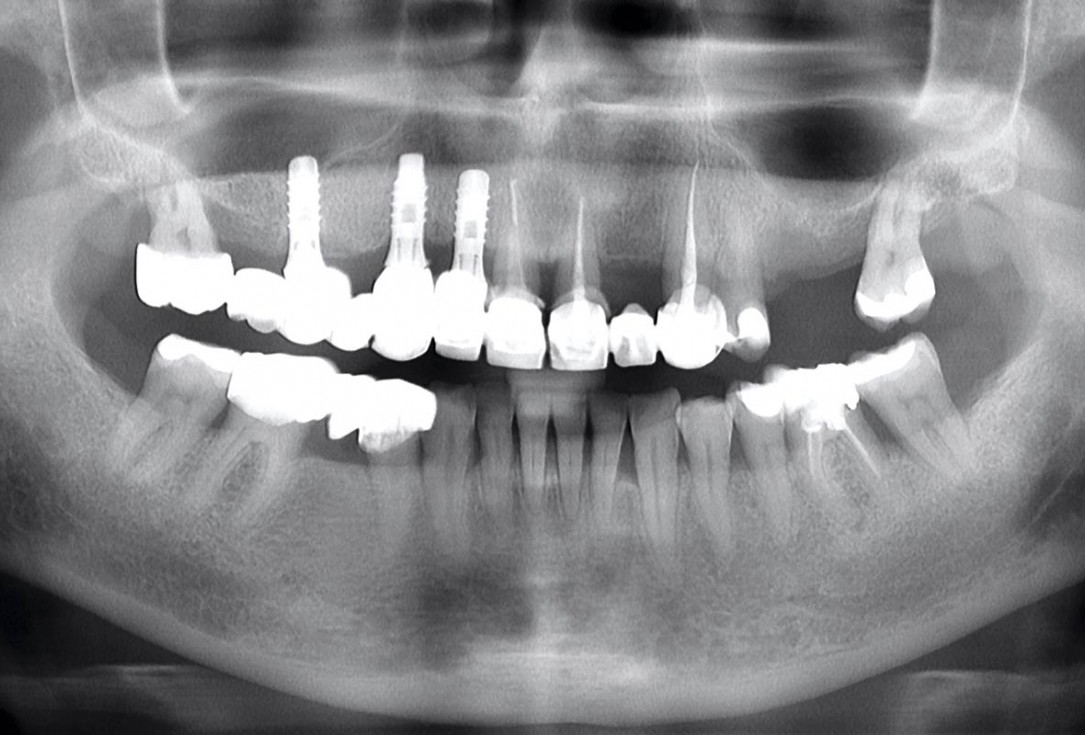

Clinical situation before extraction and implantation